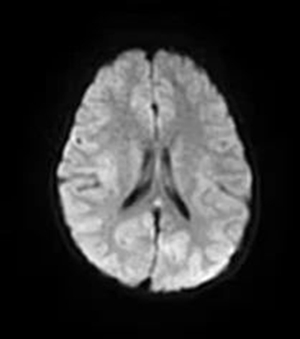

近日,6歲的佳佳(化名)持續(xù)發(fā)熱,精神狀態(tài)也不好。這天夜里,佳佳突然抽搐發(fā)作,牙關(guān)緊閉、四肢抖動,家長趕緊帶孩子到青島婦女兒童醫(yī)院就醫(yī)。神經(jīng)內(nèi)科接診醫(yī)生詳細(xì)詢問患兒病史,結(jié)合相關(guān)檢查發(fā)現(xiàn),患兒顱腦中的胼胝體壓部信號異常,診斷為可逆性胼胝體壓部病變綜合征。

胼胝體是人體左右腦中間的一束神經(jīng)組織,連接大腦左右半球之間的信息交通,使兩側(cè)大腦配合能夠更加協(xié)調(diào)。因胼胝體壓部含水量較多,當(dāng)人體病毒感染,往往比其他部位更易發(fā)生水腫、病變,進(jìn)而出現(xiàn)發(fā)熱、頭痛、精神異常、癲癇發(fā)作等表現(xiàn),可逆性胼胝體壓部病變綜合征就是一種由各種病因引起的累及胼胝體壓部的臨床影像綜合征。